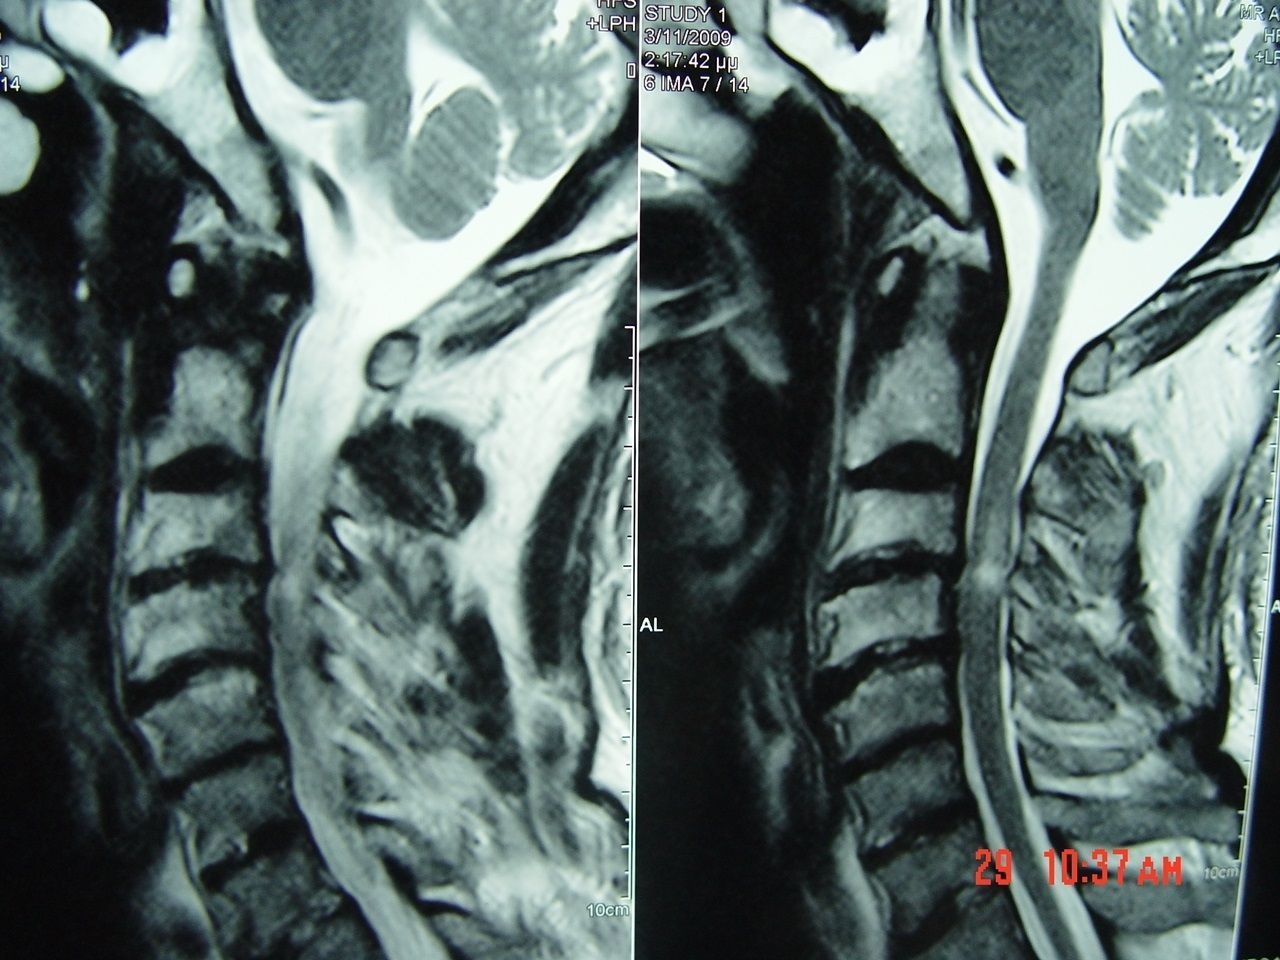

Αυχενική μυελοπάθεια Α3-4 με το χαρακτηριστικό σήμα στην μαγνητική τομογραφία.